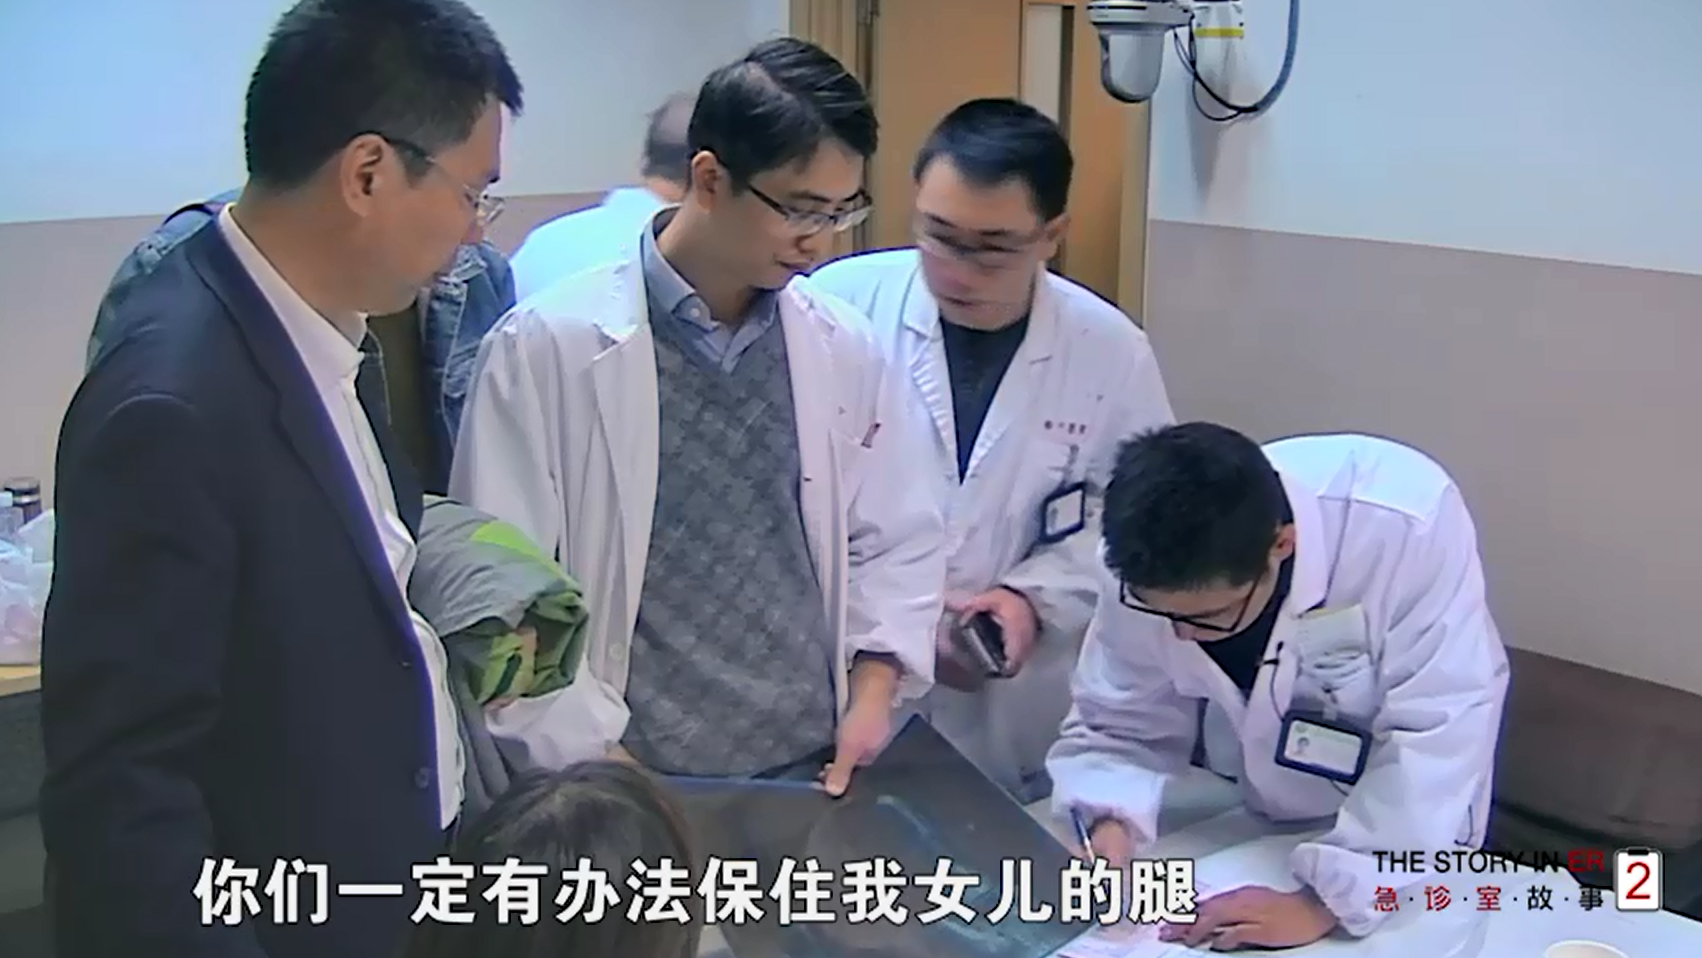

剧透《欢乐颂》:应勤被打断一条腿住院了......

别害怕,知情同意不是生死状

放心,这孩子的腿我们一定想办法保住!

大妹子,你不签字让医生怎么救你孩子??